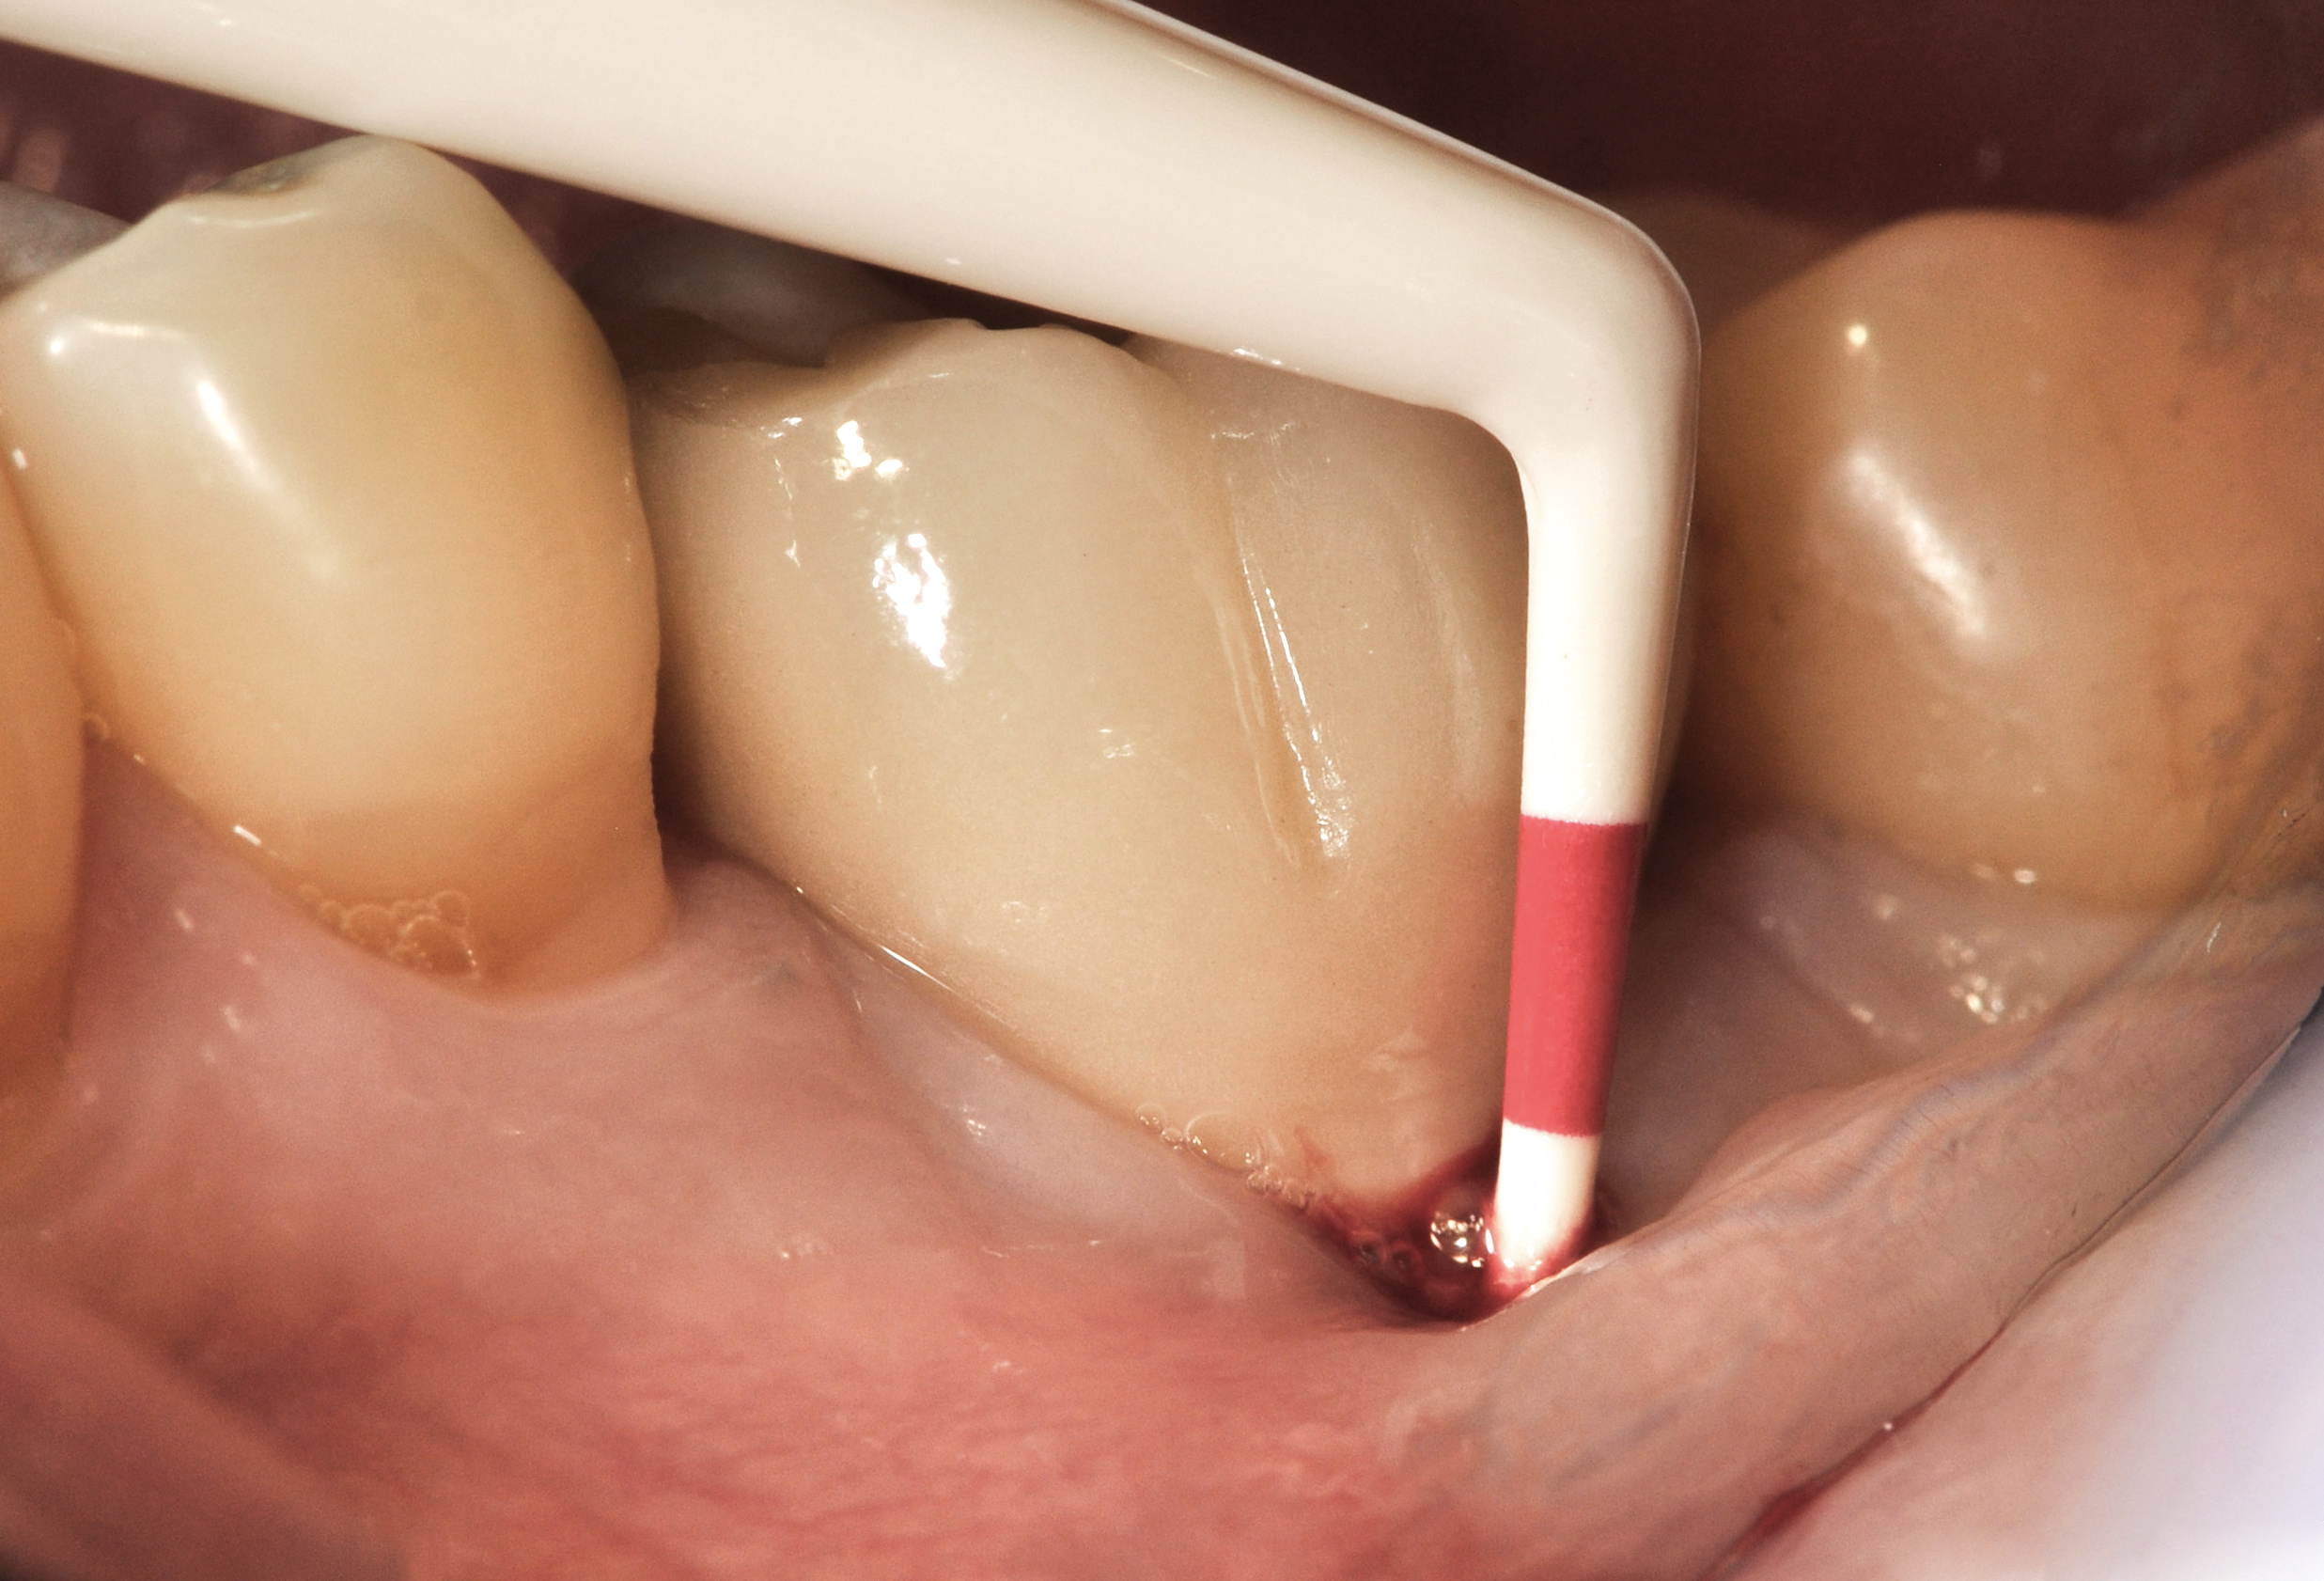

Figure 15

Fig 16. The restoration exhibited an 8-mm pocket upon probing, with bleeding on the buccal aspect.

Figure 16

Fig 17. Radiograph showed symmetrical infrabony defect affecting 50% of the implant surface.

Figure 17